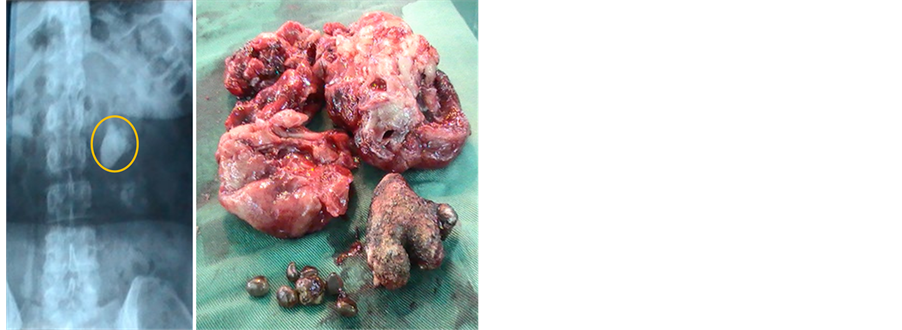

Figure 1. Bladder lithiasis on pelvic radiography without preparation (left, surrounded) and stones collected after cystolithotomy (right).

The average age of patients was 36 years, ranging from 15 months to 88 years. With a staff of 67 cases or 28.77% of urolithiasis, the age group 0 - 10 years is the most represented, followed by 11 - 20 years and 51 - 60 years (Table 1). Youth 0 - 20 years are most frequently holders of secondary urethral calculi to complications of circumcision. Table 2, Figures 1-3 show the relationship between age and location of the stones. For each age group, the male patients were significant with a sex ratio of 4.5. The distribution by age and sex also shows a male predominance (Figure 4). The socioeconomic level seems to be a predisposing factor to the development of urolithiasis (n = 122 or 52.36%). The stones affected: school students and university students (n = 64 or 27.47%), non-professionals (n = 40 or 17.17%) and middle public officials (n = 36 or 15.45%). The water from traditional wells was used by 91 patients, 110 patients consumed less than one liter of water. Figure 5 reports the different reasons for consultation. Urolithiasis (n = 17) and urogenital bilharzia (n = 11) were found as medical history. The patients diet was rich in meat (n = 200), milk (n = 160), fish (n = 150) and eggs (n = 130).

Paraclinical explorations used: ultrasonography in 181 patients or 55.7%, followed by the intravenous urography (n = 66), radiography of the pelvis without preparation (n = 63) and radiography of the abdomen without preparation (n = 15). From 233 patients whom has done urine culture, 83 showed calcium oxalate crystals and a high rate of serum calcium. All patients were subjected to: the liquid diet with absorption of at least 2 liters of water per day for adults, an anti-inflammatory and a triple antibiotic therapy in case of associated fever. During the crisis of renal colic, liquid restriction was recommended. The most practised surgery was cystolithotomy with 152 cases or 65.23% of procedures (132 cases of simple cystolithotomy, 19 cases of prostatectomy + cystolithotomy and 1 case of cystolithotomy + nephrolithotomy), followed by nephrolithotomy, renal pelvis lithotomy and nephrectomy carrying out the stones (Table 3). The aftermath of the surgery was simple, except for 2 cases of postoperative bleeding, 2 cases of suppuration of the wound, 7 cases of deaths recorded.